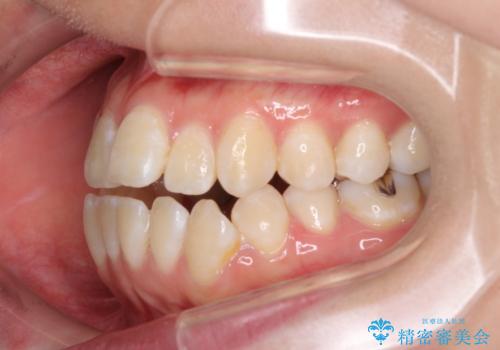

外に飛び出して磨きにくい奥歯と上下前歯の隙間 インビザラインによる矯正治療

- 上下前歯の隙間と、外側を向いていて歯磨きのしにくい奥歯を気にして来院された患者様です。

下顎前歯が1本欠損しており、上下アーチはアンバランスとなりますが、インビザラインを用いて上下の隙間を改善しながら歯列を整えることとしました。

外側を向いている奥歯は、内側にアンカースクリューを埋入して牽引の固定ゲント氏、部分的にワイヤー装置を用いることで歯列に納めることとしました。